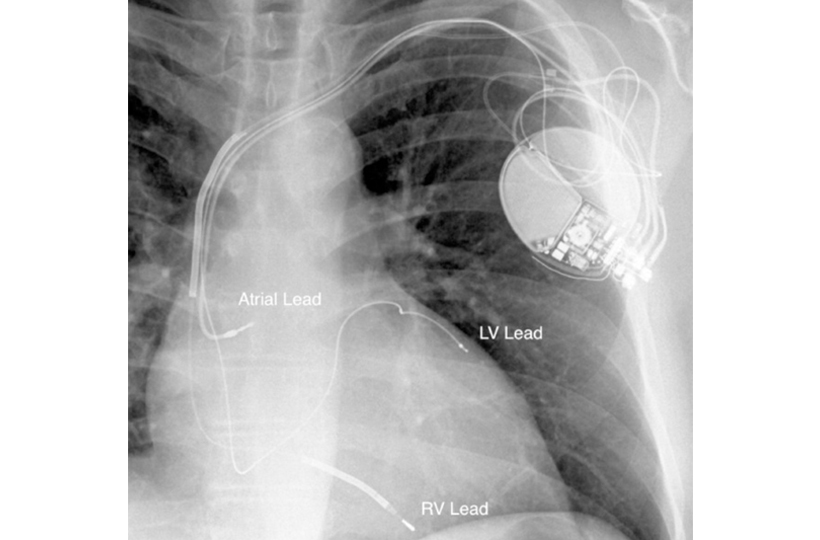

CRT involves implanting a small device, similar to a pacemaker, that delivers electrical signals to both the left and right ventricles of the heart. This ensures synchronized contractions, optimizing the heart’s ability to pump blood effectively.